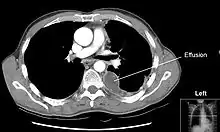

الانصباب الجنبي أو الارتشاح البِلّوري (الانسكاب البِلّوري) هو زيادة في تراكم السائل الموجود بالتجويف البِلّوري المحيط بالرئتين. تلك الكميات الزائدة من السائل يمكن لها أن تعوق التنفس عن طريق الحد من تًوًسُع الرئتين أثناء الشهيق.

الأشعات

عادةً (في الوضع الطبيعي) لا يمكن رؤية الفراغ الموجود بين طبقتي الغشاء البِلُّوري: الغشاء البِلّوري الجداري (أي المُبَطّن للقفص الصدري) والغشاء البِلّوري الحشوي (أي الذي يغطي الرئة). والارتشاح البِلّوري يتسرب ليملأ الفراغ الموجود بين هاتين الطبقتين. وبما أن الارتشاح البِلّوري له كثافة مماثلة لسوائل الجسم (أو الماء)، فإنه من الممكن رؤيته من خلال صور الأشعات. وبما أن للارتشاح كثافة أعلى من كثافة بقية الرئة (حيث أن الرئة تحتوي على الهواء) فإنه ينجذب إلى الجزء السفلي من التجويف البِلّوري. يتصرف الارتشاح البِلّوري وفقا لديناميات السوائل الأساسية، متسقاً مع شكل الرئة وتجويف الصدر. وإذا كان التجويف البِلّوري يحتوي على كل من الهواء والسائل (hydropneumothorax)، فإن السائل سيكون له مستوى أفقي "fluid level" بدلاً من أن يتسق مع مساحة الرئة.[2] لأشعات الصدر المُلتَقَطة في الوضع الجانبي lateral decubitus position (أي مع وضع المريض على جانبه أثناء التقاط الأشعة) حساسية أكبر، ويمكنها الكشف عن وجود الارتشاح في حال وجود حتى اقل من 50 مل من السوائل. يلزم وجود 300 مل على الأقل من السوائل حتى يتسنى لأشعات الصدر في الوضع القائم (upright position) الكشف عن بعض علامات الارتشاح البِلّوري (على سبيل المثال، التحام الزاوية بين الضلوع والحجاب الحاجز costophrenic angle).